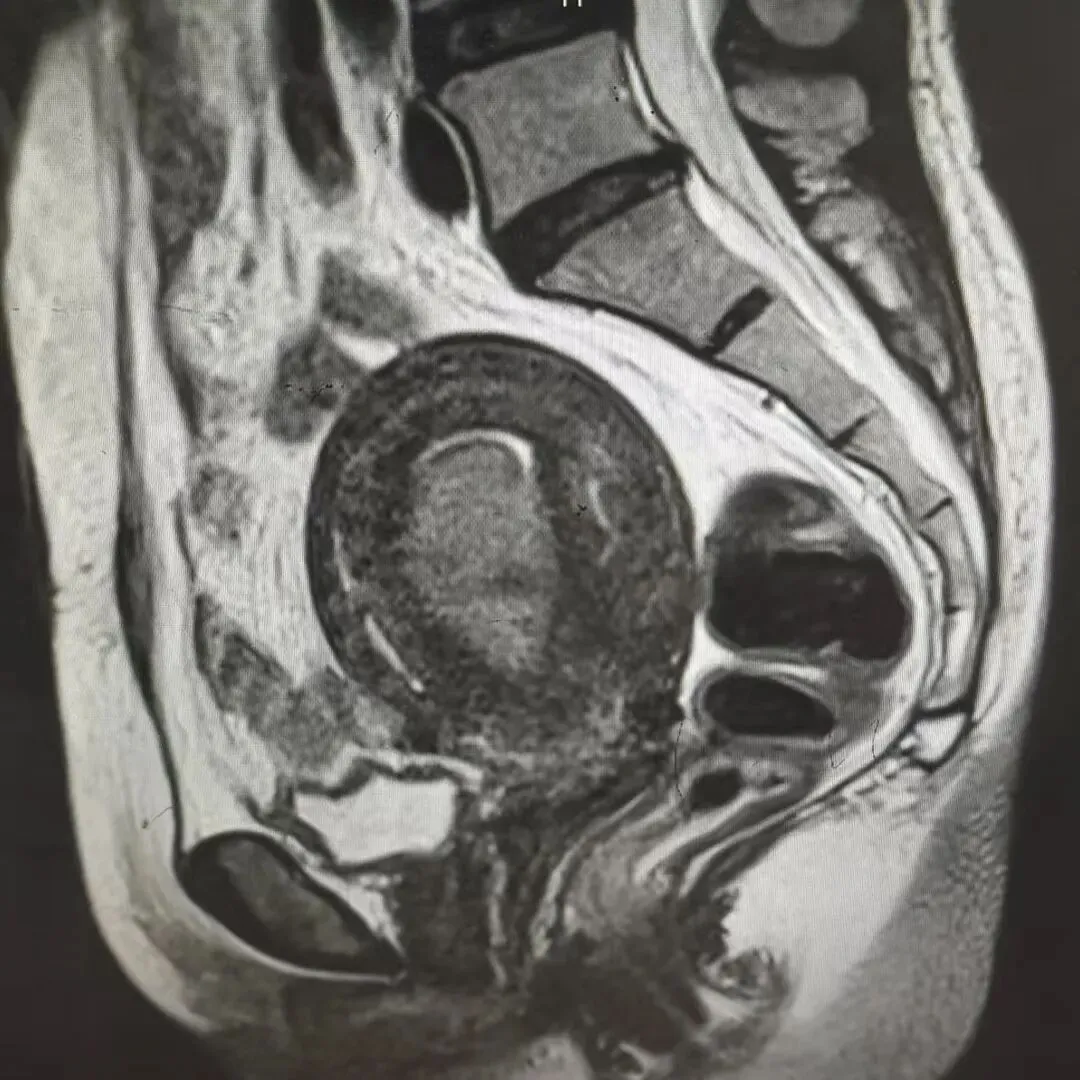

案例四:患者因“阴道出血十余天”入院。彩超示:宫腔内探及一大小约40mm*26mm低回声,提示子宫粘膜下肌瘤。在静脉麻醉下进行了宫腔镜下探查术,术中见子宫前壁一大小约直径3cm肌瘤凸起,行肌瘤电切术,手术顺利。术后病理报告诊断为子宫平滑肌瘤。术后恢复好,痊愈出院。